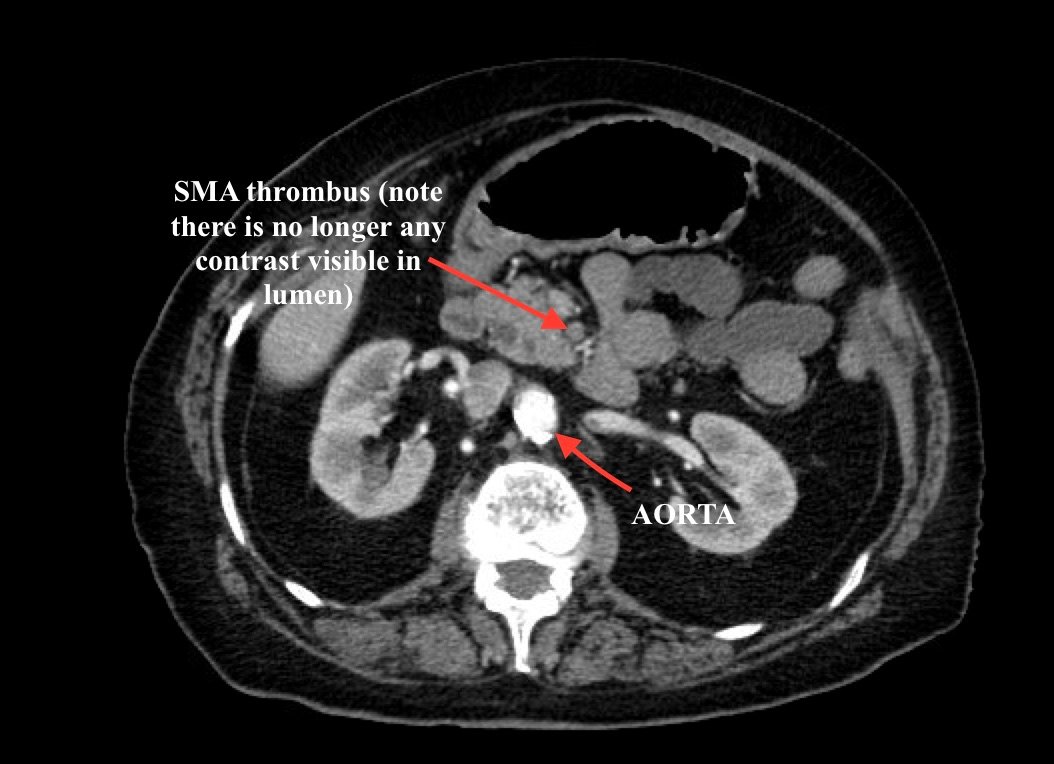

Computed tomography (CT) angiogram of the abdomen and pelvis revealed a superior mesenteric artery (SMA) thrombosis 5 cm from the origin off of the abdominal aorta. As seen in the sagittal view, there does not appear to be any contrast 5 cm past the origin of the SMA. On the axial views, you can trace the SMA until the point that there is no longer any contrast visible which indicates the start of the thrombus. The SMA does not appear to be reconstituted. There was normal flow to the celiac artery. (See annotated images).